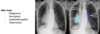

Pneumothorax